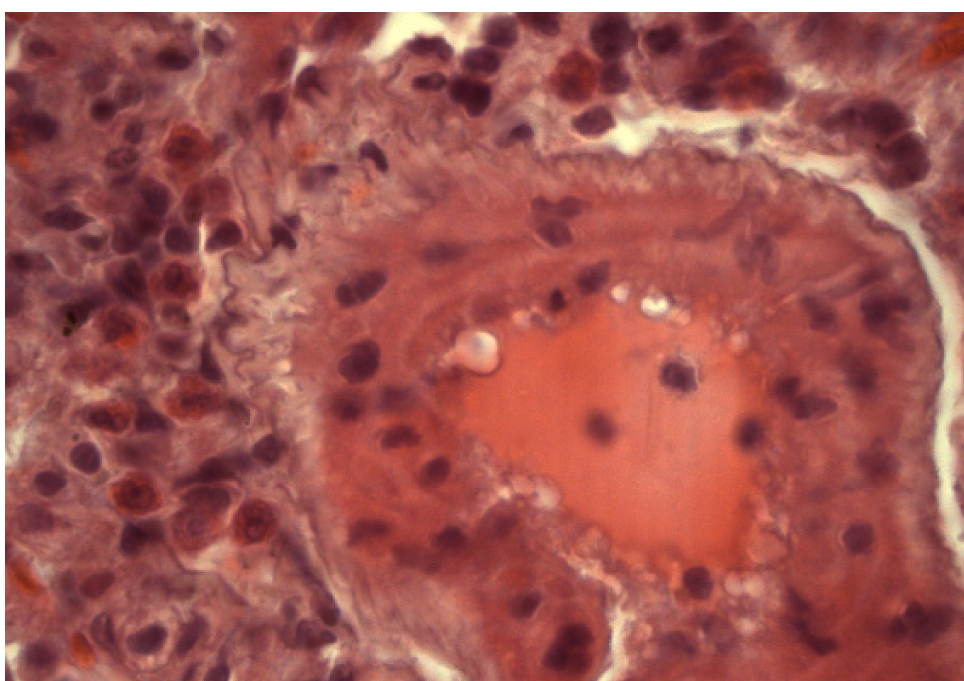

Артерии полнокровны. В их просветах наблюдается гемолиз эритроцитов. В адвентициальной оболочке сосудов выявляются полиморфноцитарные инфильтраты, содержащие эозинофилы (рис. 11), что может служить доказательством развития аллергических реакций.

Рис. 11. Группа 8. Гемолиз эритроцитов в просвете артерии. Периваскулярный инфильтрат, содержащий эозинофилы. Окраска гематоксилином и эозином. Ок. 10. Об. 100. Иммерсия

Крупные скопления многоядерных макрофагов в межальвеолярных перегородках легочной ткани свидетельствуют о выраженной макрофагальной реакции. Наличие фибробластов, активно продуцирующих коллагеновые волокна, подтверждает фиброгенные свойства фталата свинца. Присутствие эозинофилов в полиморфноклеточных инфильтратах указывает на способность фталата свинца вызывать сенсибилизацию организма. Все вышеперечисленное является доказательством развития хронических воспалительных процессов.